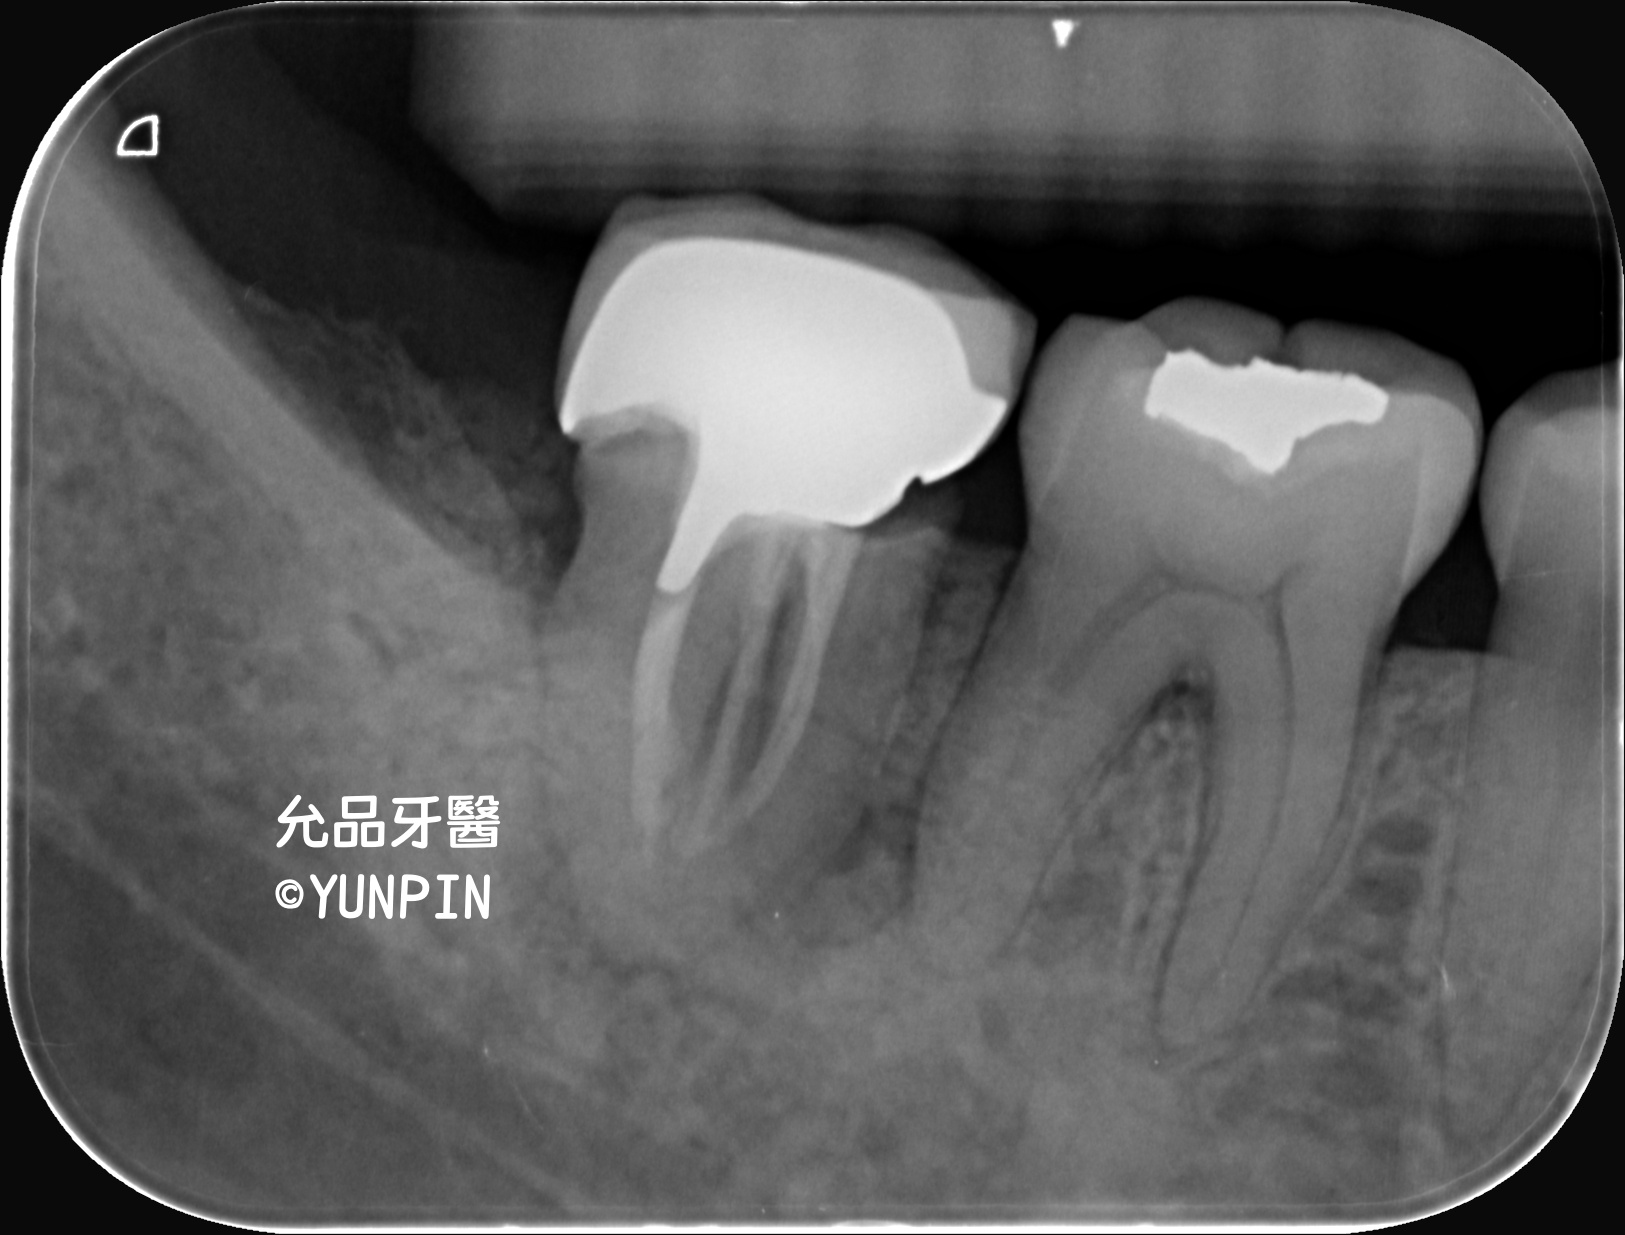

患者主訴牙齒附近牙齦腫不適感多,檢查為牙齒斷裂至根部

進行手術拔除並施作齒槽骨脊保存術。

右下第二大臼齒